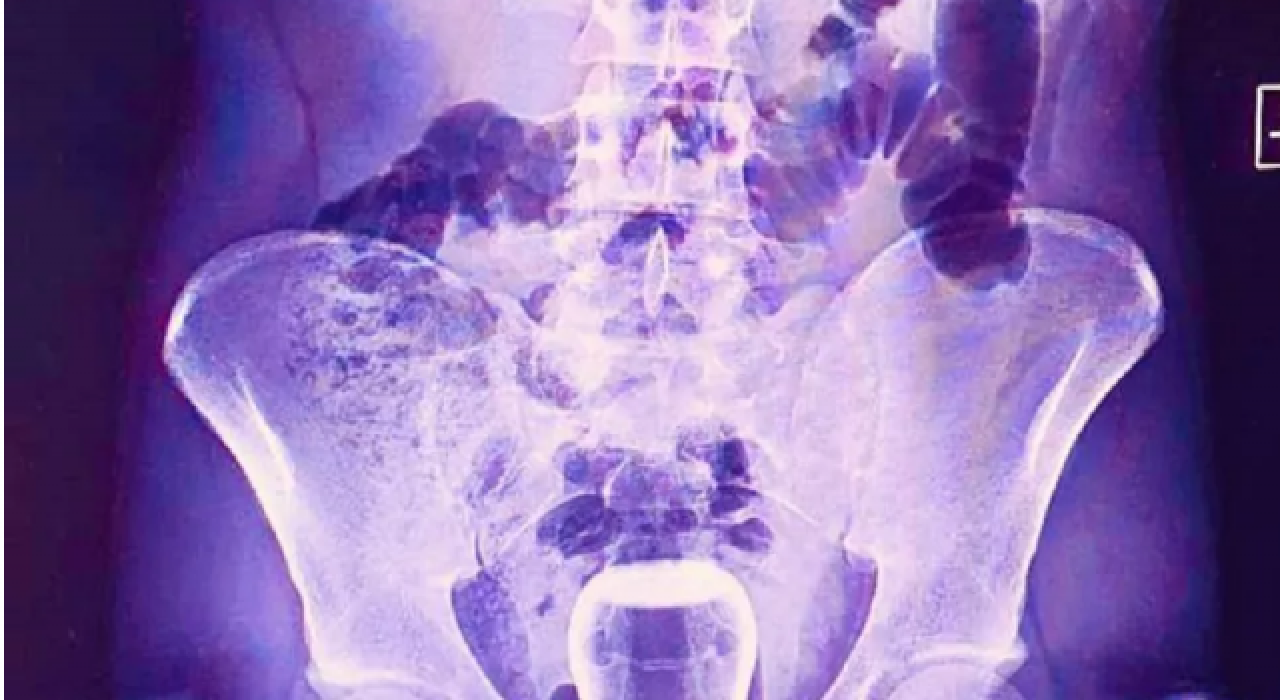

Şanlıurfa'da basur hastası olan bir kişinin iddiaya göre tedavi için hacamat yaptırırken yağlı çay bardağı anüs bölgesine kaçtı. Bardak ameliyatla çıkarıldı.

İsmi açıklanmayan bir kişi Mehmet Akif İnan Eğitim ve Araştırma Hastanesi'ne başvurdu. Acil serviste hastanın çekilen röntgeninde anüs bölgesinde çay bardağı görüldü.

Bu kişi genel cerrahi servisinde ameliyata alındı. Çay bardağı, uzman doktorlar tarafından gerçekleştirilen operasyonla çıkarıldı.

Ameliyatla sancıdan kurtulup eski sağlığına kavuşan hasta doktorlara, uzun zamandır basur hastası olduğunu, hacamatçıya gittiğini ve yağlı çay bardağın kazayla anüs bölgesine kaçtığını ileri sürerek, ameliyattan dolayı teşekkür etti.